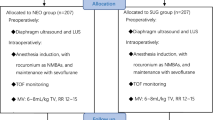

All patients underwent ultrasound examinations of the diaphragm at baseline (the day prior to surgery), 3 days after surgery and 10–14 days after surgery as illustrated in Fig. 1. Phrenic nerve conduction measurements were performed at the same time points in a subset of patients. Participation was not conditional on participation in phrenic nerve conduction measurements as stimulation of the nerve may cause discomfort.

We enrolled 40 patients between August 2020 and October 2021. Baseline characteristics are shown in Table 1, and selected intraoperative data are shown in Supplemental material 3. Esophageal resection surgery was performed in 27 patients, and pulmonary lobectomy was performed in 13 patients. Thirty-four patients underwent right-sided surgery, and six patients underwent left-sided surgery. Of the 34 patients undergoing right-sided surgery, 18 patients had VATS performed. A flowchart of patient examinations is shown in Fig. 1. There was a total of 82 PPCs of which the most common were pleural effusion (n = 28) hypoxemia (n = 14), atelectasis (n = 10), pneumonia (n = 8), and prolonged use of CPAP/NIV (n = 11).